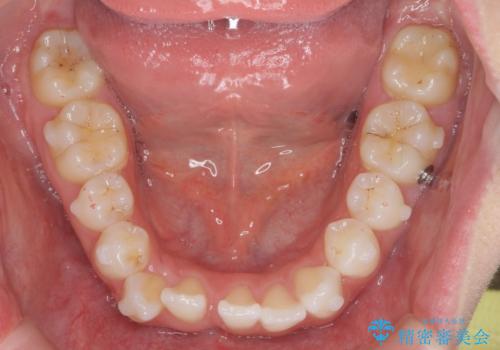

- 前歯が出っ歯のように見えることの改善を求めて来院されました。

当初、セラミックによる治療をご希望されていましたが、相談の結果矯正治療を選択されることとなりました。

通常口元の突出感の改善を行うには小臼歯の4本抜歯が検討されますが、歯のガタ付きが下顎前歯に限定していることから

下顎前歯を1本だけ抜去を行い、上顎の歯は可及的にマイクロインプラントを用いた後方移動を行い口元の印象の改善を計画することとなりました。

マイクロインプラントを用いてしっかりと後方移動を行ったことで前歯の角度は改善され、口元もすっきりと仕上げることができました。